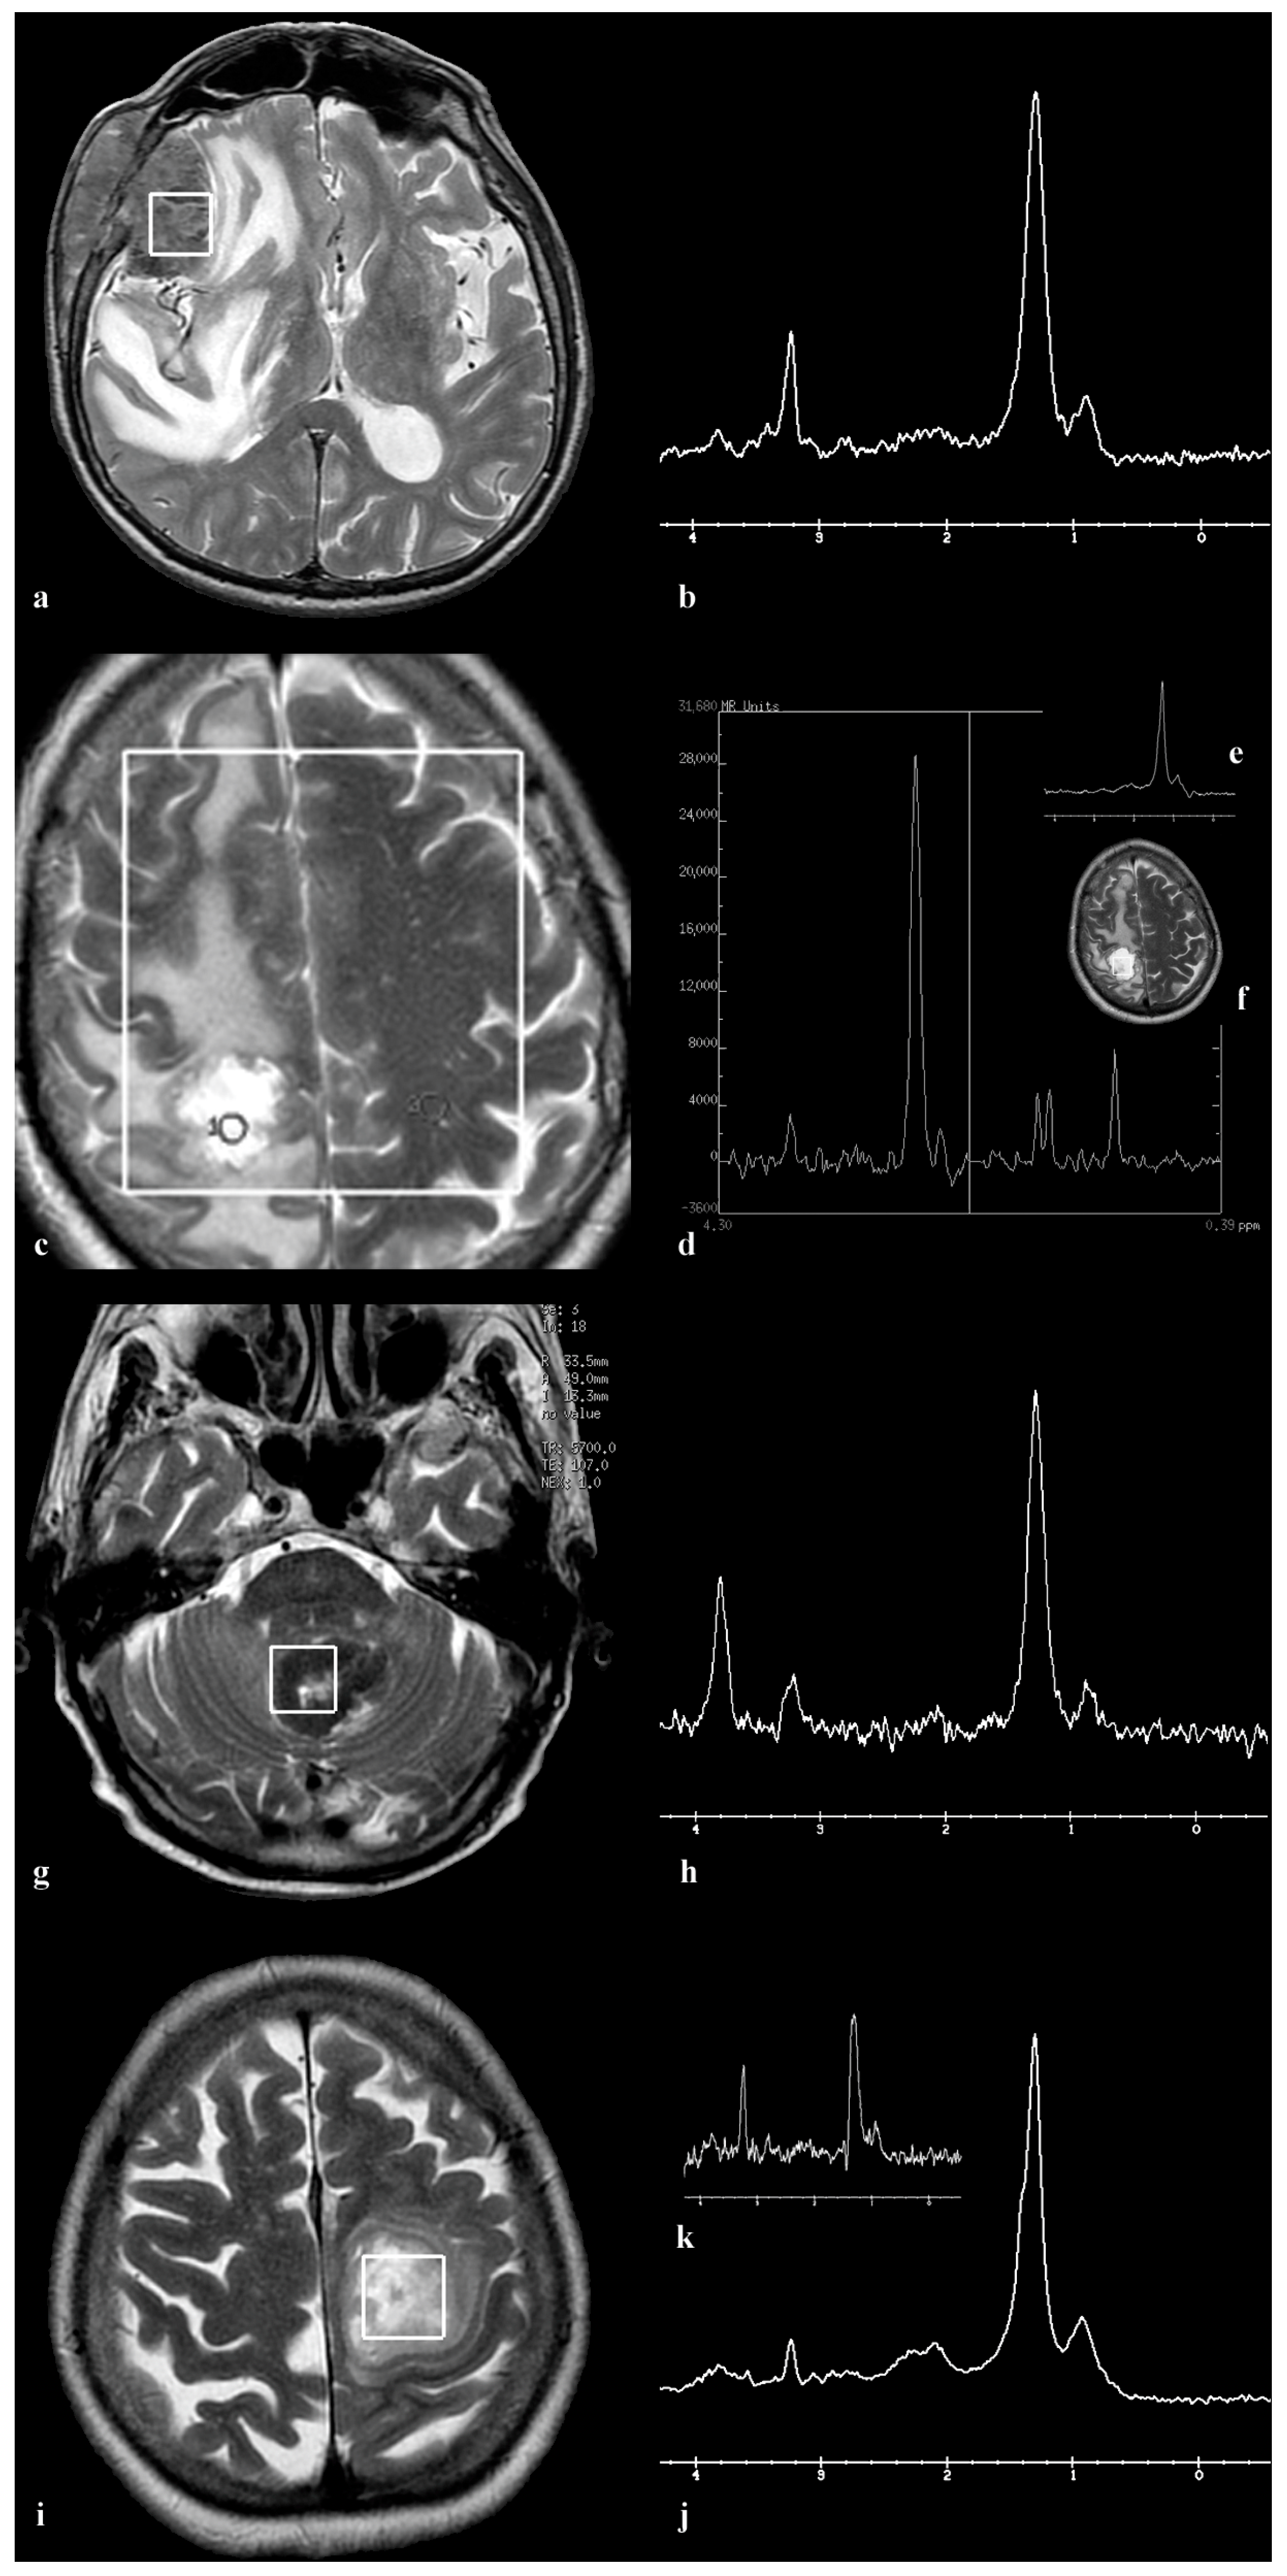

3.1. Patient 1

3.2. Patient 2

3.3. Patient 3

3.4. Patient 4

3.5. Patient 5